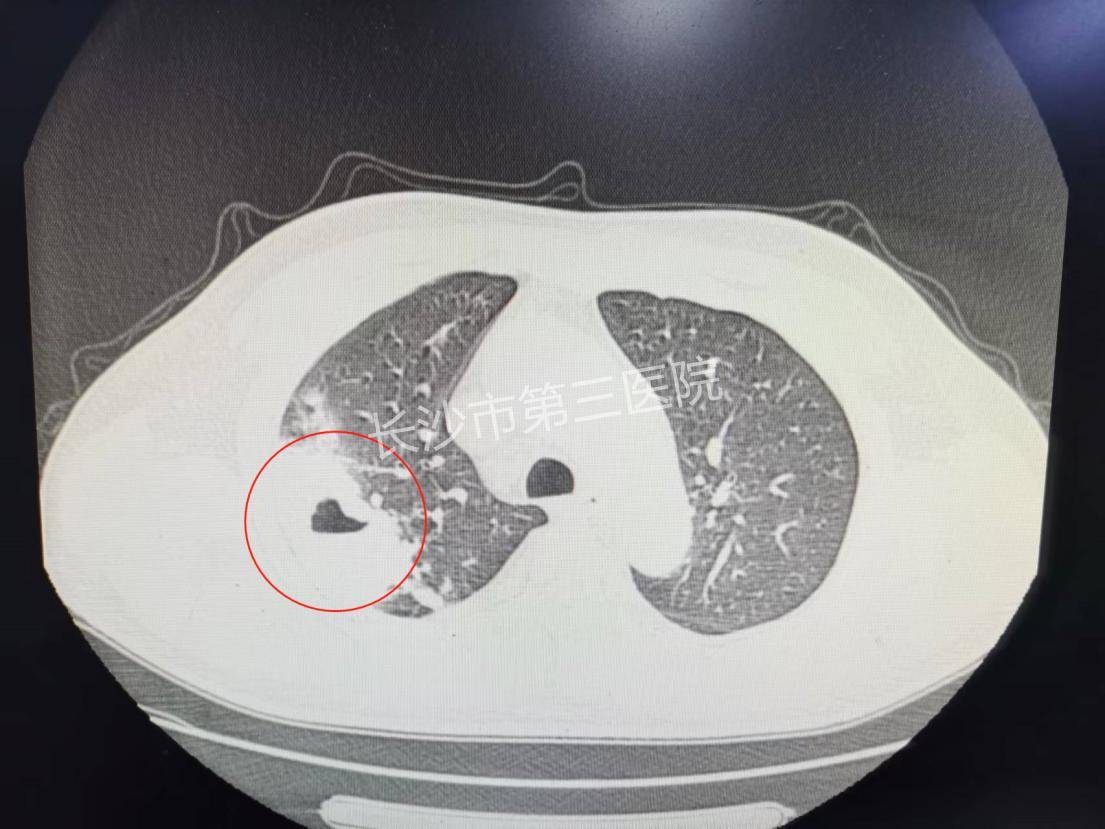

没把咳嗽当回事长沙52岁大叔肺上咳出拳头大窟窿